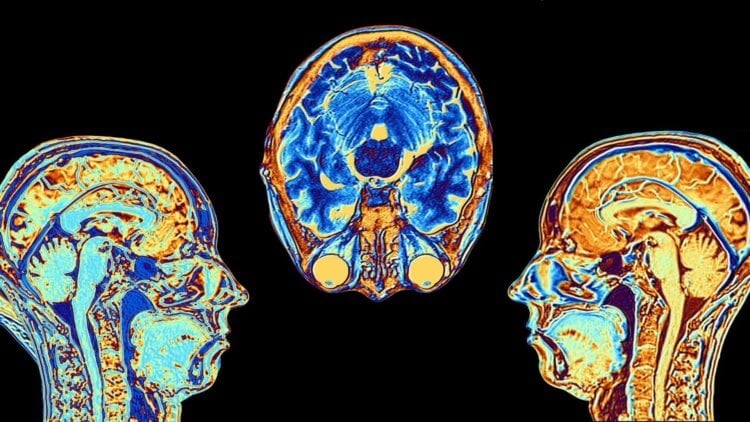

Еще в 2010 году нейробиологи Массачусетского технологического института показали, что они могут влиять на суждения людей, вмешиваясь в активность в определенной области мозга Это открытие, по их мнению, помогает понять, как мозг "конструирует мораль". Область мозга, известная как правый височно-теменной узел, очень активна, когда мы думаем о намерениях, мыслях и убеждениях других людей. Ученые нарушили активность в этой части мозга, индуцируя ток с помощью магнитного поля, воздействующего на кожу головы. Они обнаружили, что способность испытуемых выносить моральные суждения, требующие понимания намерений других людей — например, неудавшейся попытки убийства — была нарушена. Исследователи использовали неинвазивную технику, известную как транскраниальная магнитная стимуляция, для избирательного вмешательства в активность мозга. Магнитное поле, воздействующее на небольшой участок черепа, создает слабые электрические токи, которые препятствуют нормальному функционированию близлежащих клеток мозга.

Лиан Янг, научный сотрудник отдела мозга и когнитивных наук, считает, что это часть мозга имеет решающее значение для вынесения моральных суждений: «Вы думаете о морали как о поведении действительно высокого уровня. В нормальных обстоятельствах люди очень уверены и последовательны в такого рода моральных суждениях. Возможность воздействовать (магнитным полем) на определенную область мозга и изменять моральные суждения людей — это удивительно. Это не полностью меняет моральные суждения людей, а только искажает их».